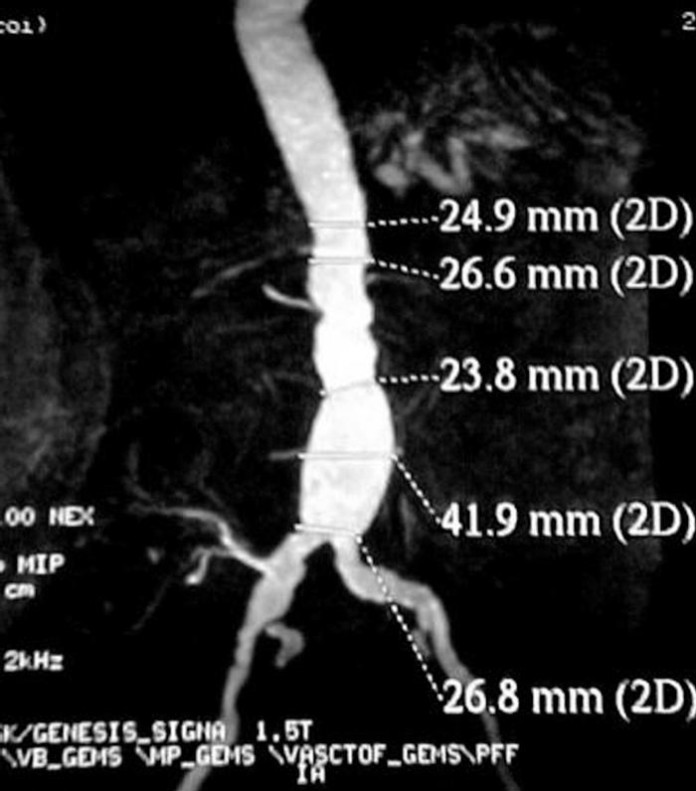

Un aneurisma aórtico abdominal es una protuberancia en la pared de la parte de la aorta, la arteria más grande del cuerpo. Si un aneurisma se rompe, existe un alto riesgo de muerte por hemorragia. Ultrasonido de detección puede detectar la condición.